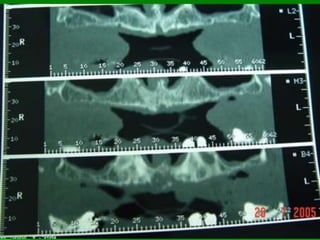

Tomografia linear

Tomografia computadorizada

T.C.

TC